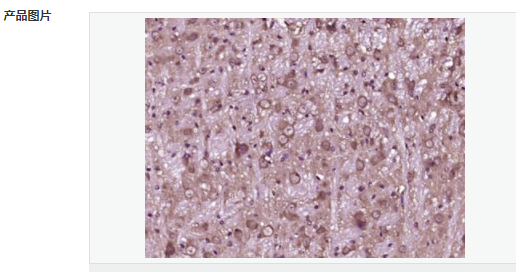

| 產品應用 | WB=1:500-2000 ELISA=1:5000-10000 IHC-P=1:100-500 IHC-F=1:100-500 IF=1:100-500 (石蠟切片需做抗原修復) not yet tested in other applications. optimal dilutions/concentrations should be determined by the end user. |

| 產品介紹 | BM88 is a 149 amino acid protein that belongs to the CEND1 familly. Involved in neuroblastoma cell differentiation, BM88 is a single-pass type IV membrane protein that is neuron specific. It is suggested that BM88 forms a dimer of two identical polypeptides linked by disulfide bridges. BM88 has a central proline-rich region containing four PxxP motifs, which typically bind SRC homology-3 (SH3) domains, as well as a putative C-terminal transmembrane region, and several potential sites for N-glycosylation, myristoylation and phosphorylation. It is also suggested that a novel signaling mechanism exists by which BM88 interferes with calcium release from inositol 1,4,5-trisphosphate-sensitive stores and exerts anti-proliferative and anti-apoptotic functions. BM88 is an important molecular target for HDAC inhibition, and transcription of BM88 is induced by trichostatin-A. Function: CEND1 is a neuron-specific protein. The similar protein in pig enhances neuroblastoma cell differentiation in vitro and may be involved in neuronal differentiation in vivo. Multiple pseudogenes have been reported for this gene. Subunit: Homodimer Subcellular Location: Membrane; Single-pass type IV membrane protein. Tissue Specificity: Neuron specific. Similarity: Belongs to the CEND1 family. SWISS: Q8N111 Gene ID: 51286 Database links: Entrez Gene: 51286 Human Entrez Gene: 57754 Mouse Omim: 608213 Human SwissProt: Q8N111 Human SwissProt: Q9JKC6 Mouse Unigene: 22140 Human Unigene: 87027 Mouse Unigene: 64460 Rat Important Note: This product as supplied is intended for research use only, not for use in human, therapeutic or diagnostic applications. |